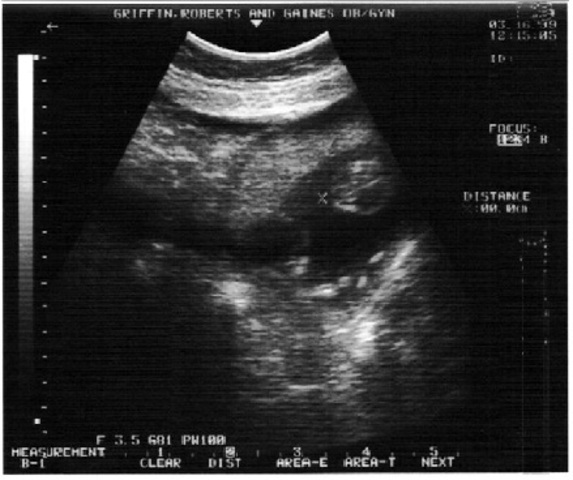

• Bones are visible.  Heartbeat can be heard with a stethoscope.

Bones are visible. Heartbeat can be heard with a stethoscope.

4 to 6 months after conception, a fetus's bones are visible, and its heart can be heard with a stethoscope.